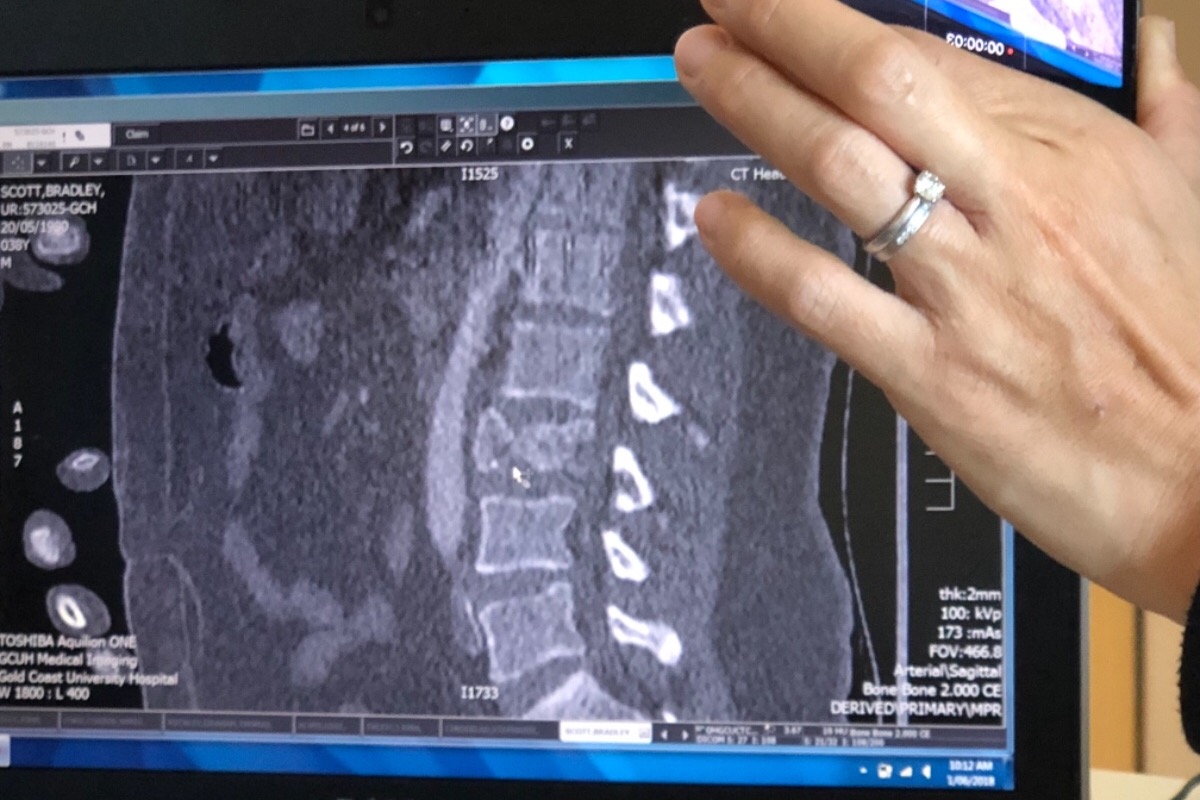

On Fri 25th June I had a Paragliding accident where I ended up breaking 2 arms, a leg and minor spinal injuries.

I require 3 operations over the coming weeks including spinal op today.